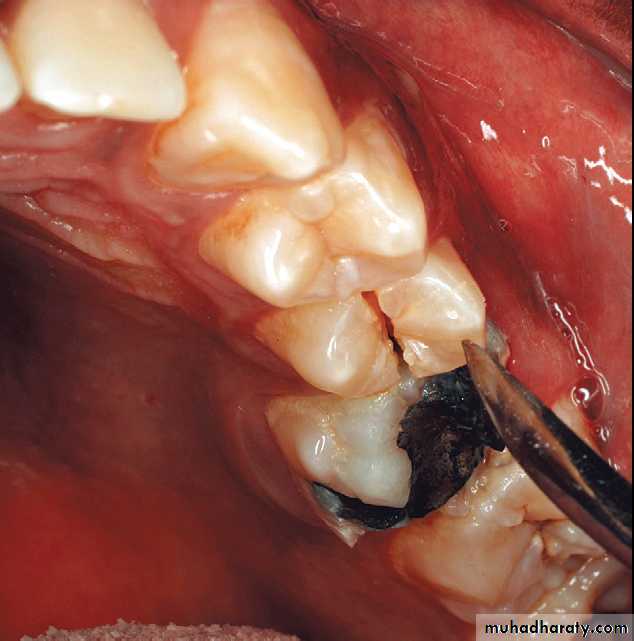

Nonreduced dentoalveolar fracture of the left posterior mandible interfering with occlusion.